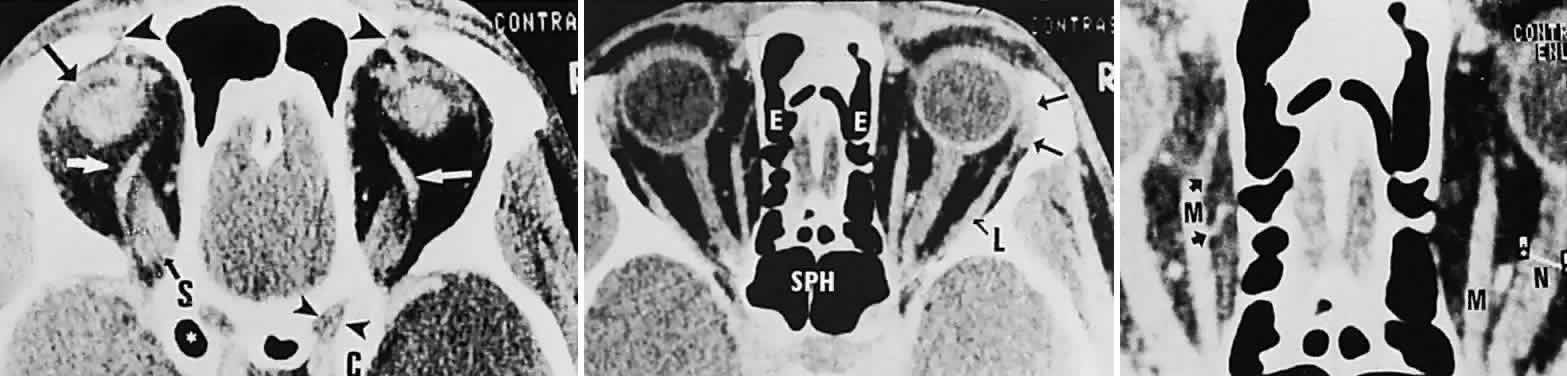

Computed tomography (CT) is presently the single most productive modality for analyzing orbital bones, with which the following structures may be visualized: the bony confines of the orbit and surrounding sinus structures; the lacrimal bony canal; the globe and lens; the intraorbital portions of the optic nerve; and the extraocular muscles, especially the horizontal and superior recti (Fig. 16). Moreover, CT with contrast enhancement discloses the full configuration and location of masses with respect to other orbital structures, principally the relationships to muscle cone, optic nerve, and lacrimal gland. In several particular instances, the location, configuration, and degree of contrast enhancement of lesions may strongly suggest a distinctive tumor type (Fig. 17) or inflammation (e.g., cavernous hemangioma, optic glioma, lacrimal gland tumor, dermoid cyst, mucocele, perioptic meningioma, single or multiple muscle thickening),65–67 but no firm histopathologic diagnosis may be inferred by CT characteristics alone.

Fig. 16. Contrast-enhanced CT scan of normal orbits. Top. Superior orbit section shows superior ophthalmic veins (white arrows), superior rectus origin (S), left levator muscle complex (black arrow), position of trochlea and tendon of superior oblique muscles (large arrowheads), right optic canal (small arrowheads), and anterior clinoid (C). (*, pneumatized left anterior clinoid.) Middle. Midorbital section shows ethmoidal sinus complex (E), sphenoidal sinus (SPH), lacrimal gland (arrows), and lateral rectus (L). Bottom. Enlargement shows left medial rectus (M), with anterior (top arrow) and posterior (bottom arrow) ethmoidal arteries; note cursor across optic nerve on right (N).

Fig. 17. CT scan shows typical configuration of intraconal hemangioma. Note slightly inhomogeneous content, rounded distinct borders, and clear apical space.